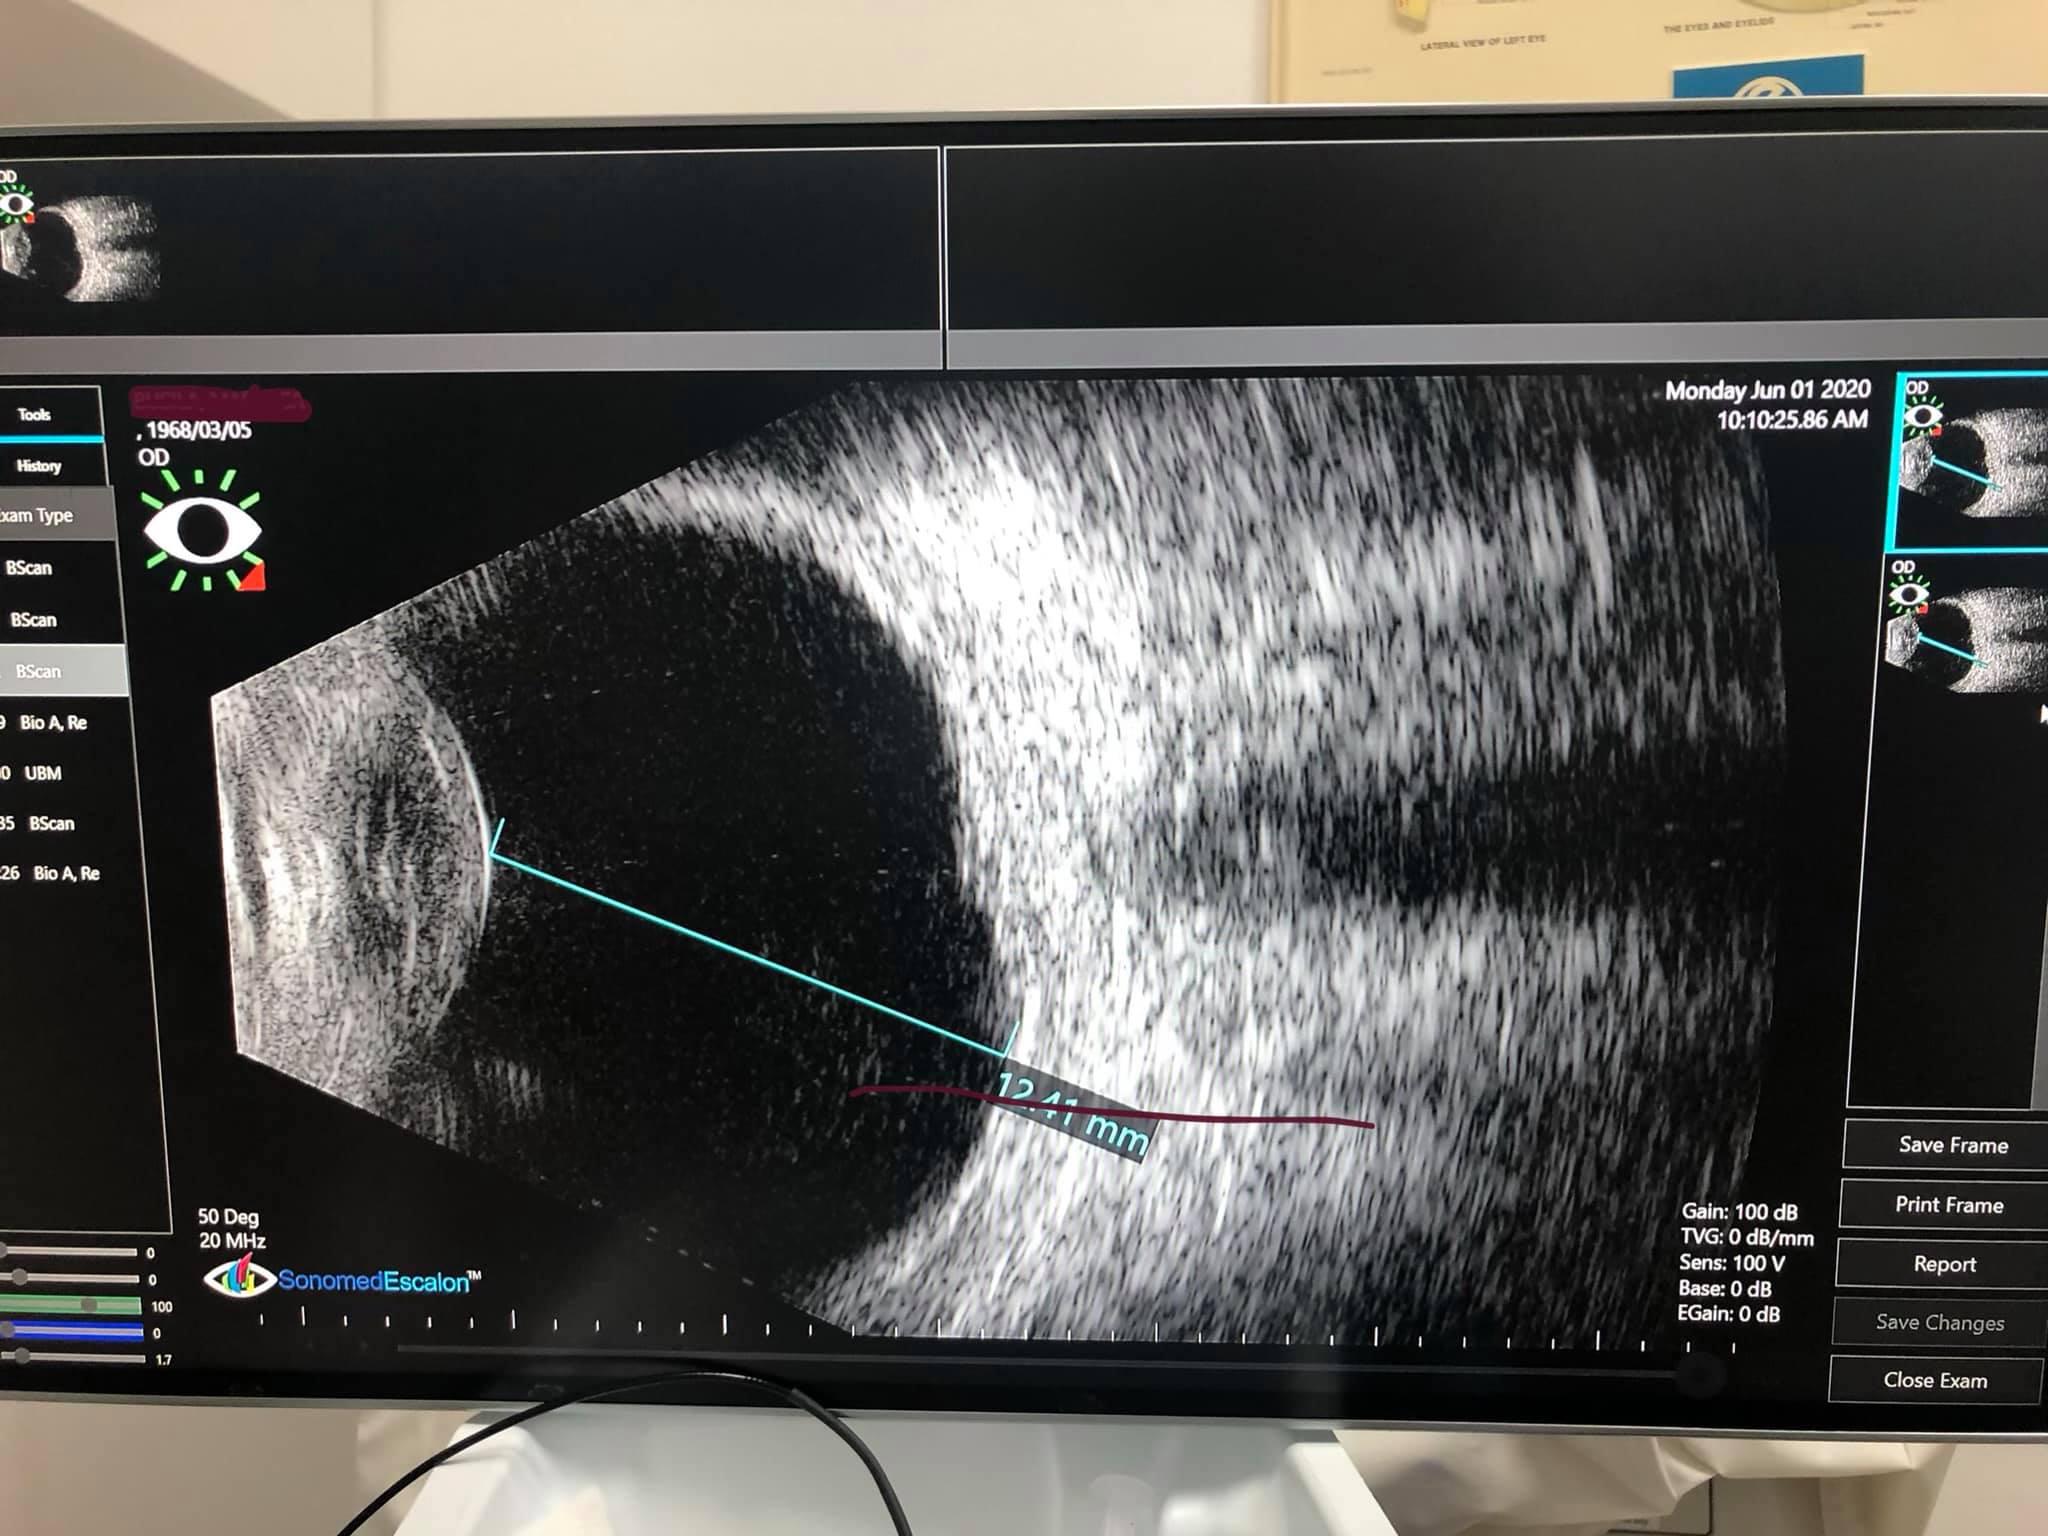

Din păcate, frecvent se întâmplă ca fundul de ochi să nu poată fi vizualizat, nici clinic, nici tomografic, din cauza unor opacități avansate la nivelul polului anterior (cataractă avansată sau leucoame corneene semnificative); în aceste situații, ecografia de pol posterior poate să ne dea o idee despre starea fundului de ochi, fără a fi, însă, capabilă să ne dea detalii despre anumite afecțiuni maculare. În schimb, ecografia oculară e esențială în diagnosticarea unor afecțiuni din periferia retinei, unde examenul clinic și tomografic ajung mai greu și ale unor boli precum dezlipirea de retină, retinoschizis-ul, decolarea de coroidă, prezența de corpi străini intraoculari, prezența sângelui în cavitatea vitreeană, tumori oculare, decolări maculare severe sau afecțiuni de nerv optic (drusen, excavații mari patologice, etc).